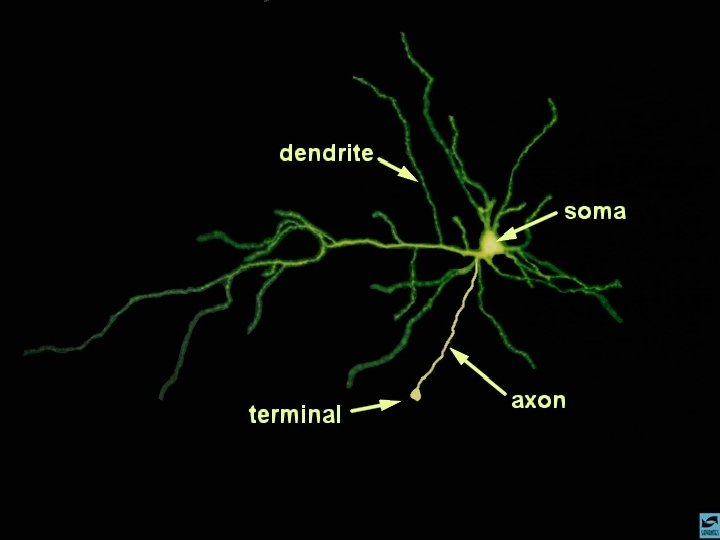

A AÇÃO DAS DROGAS NO SISTEMA NERVOSO CENTRAL O TECIDO CEREBRAL Neurônio Células da glia

A AÇÃO DAS DROGAS NO SISTEMA NERVOSO CENTRAL O NEURÔNIO Axônio (pré-sinapse) Dendritos (pós-sinapse)

A AÇÃO DAS DROGAS NO SISTEMA NERVOSO CENTRAL A COMUNICAÇÃO ENTRE OS NEURÔNIOS

A AÇÃO DAS DROGAS NO SISTEMA NERVOSO CENTRAL A SINAPSE